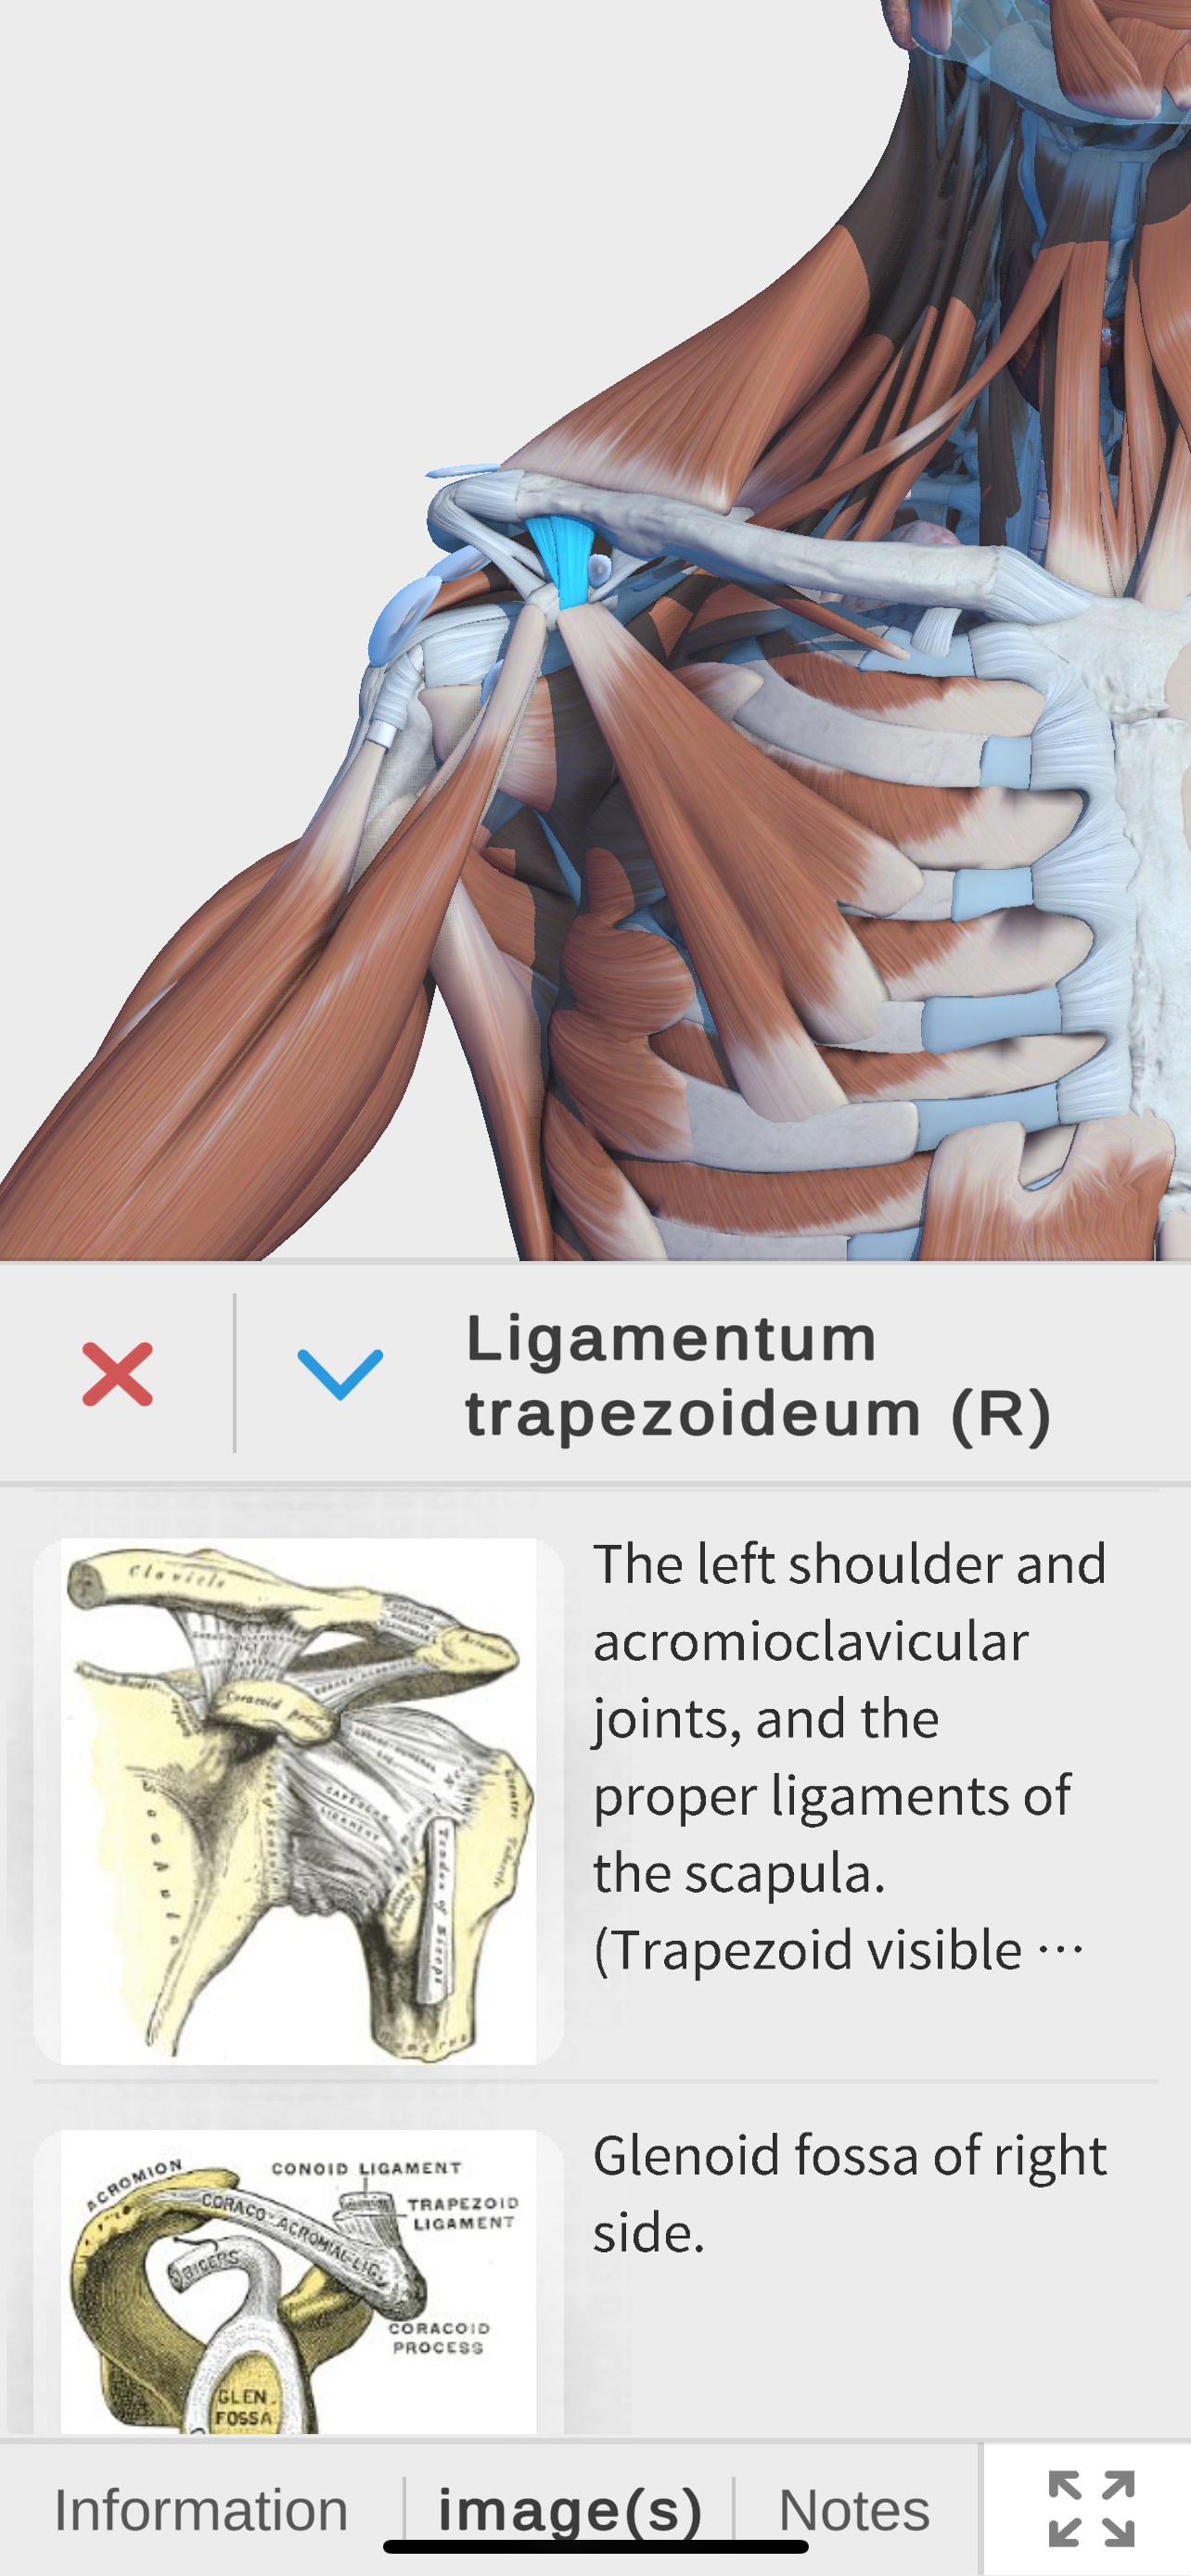

Complete and easy-to-use virtual guide for learning, understanding, and visualizing the complexities of human anatomy in 3D. Includes information and images for each anatomical system and part, multiple options to interact with the 3D anatomy models (hiding, fading, etc), and much more.

We believe that learning by interaction is the best and easiest way to study human anatomy.

- highly detailed

- see details for each body part

Hi-res imagery everywhere you need it

- Ligamentous